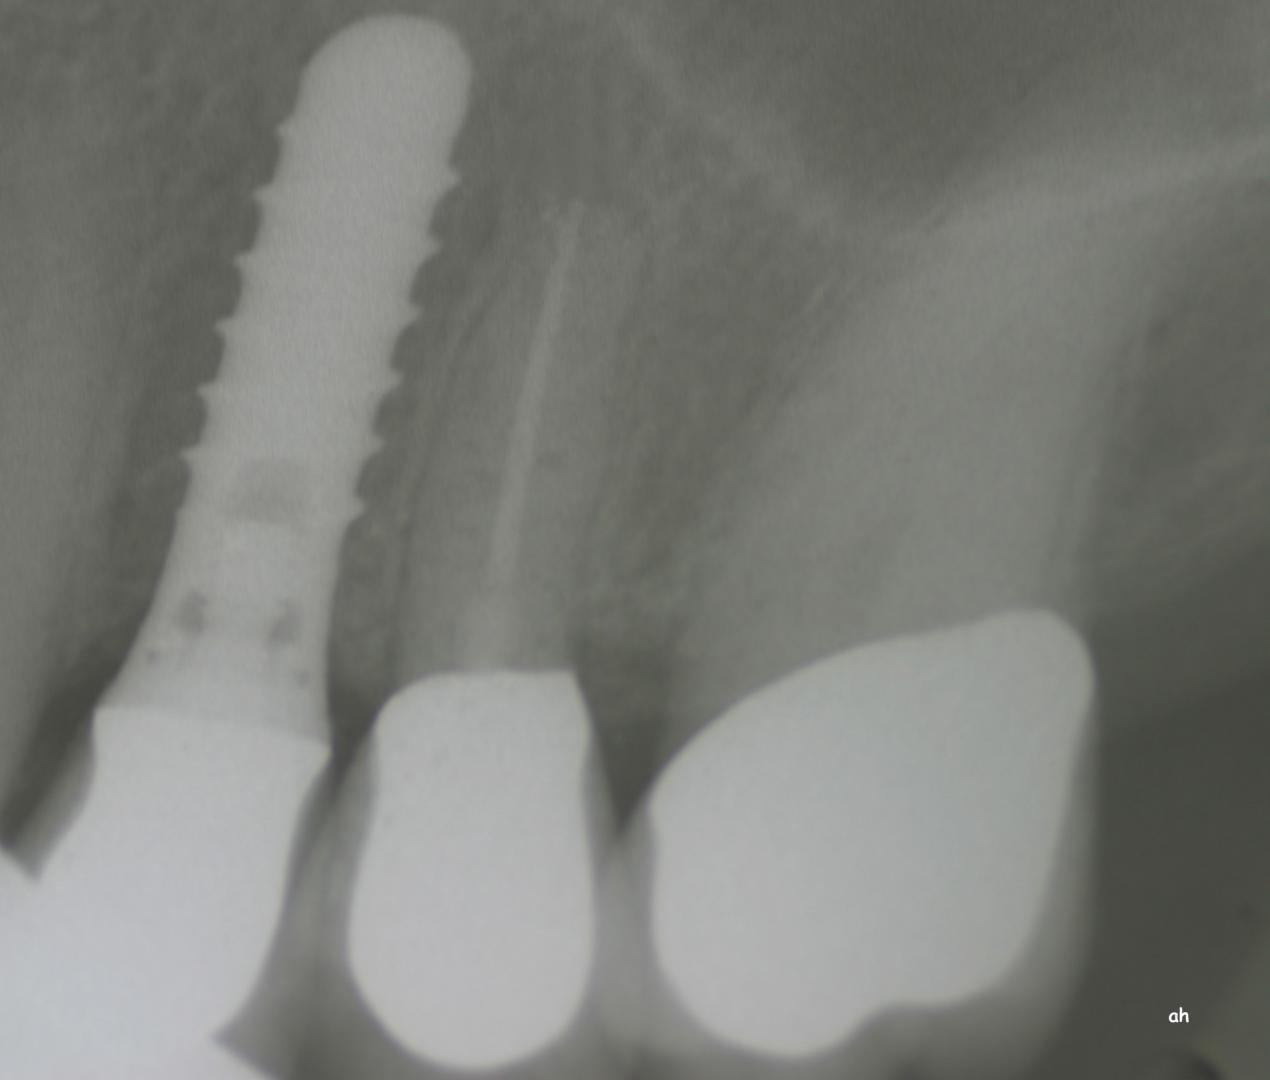

Exemple 11: Pendant l'implantation on remarque un manque d'os sur la partie externe, les spires de l'implant sont visibles.

Exemple 11: Une greffe d'os est effectuée afin de compenser l'épaisseur d'os manquante.

Exemple 11: Le tout est recouvert d'une membrane collagène.

Exemple 11: Après cicatrisation environ 6 mois, le moignon est vissé sur l'implant.

Exemple 11: La couronne céramique en place.